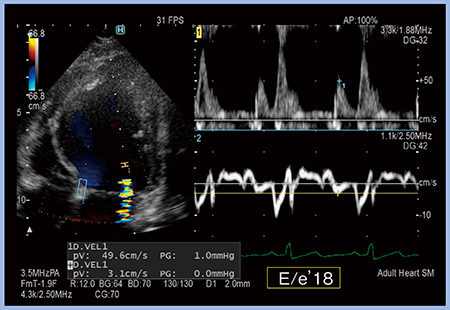

症例2について,同一心拍で2か所のドプラ波形を同時に計測可能な“Dual Gate Doppler”で計測すると,E/e’は18と高値であった(図3)。

図3 Dual Gate Doppler(症例2)